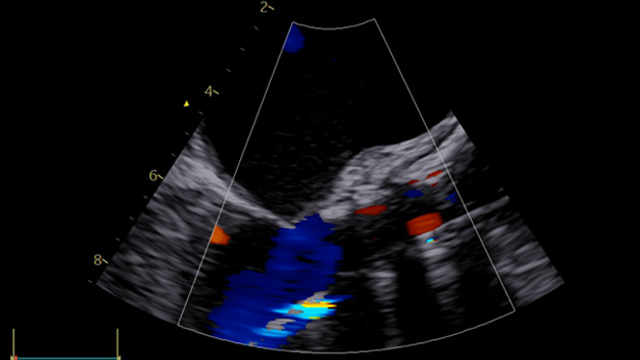

Valve in valve in small degenerative surgical bioprosthesis - LIVE case

A 74-year-old female with a permanent pacemaker and preserved LV function presented with a symptomatic degenerative surgical valve (SJ Epic 21) implanted in 2016.

Patient underwent implantation of an Evolut FX 26 mm under general anesthesia with cerebral embolic protection and TEE guidance. A surgical valve fracture...